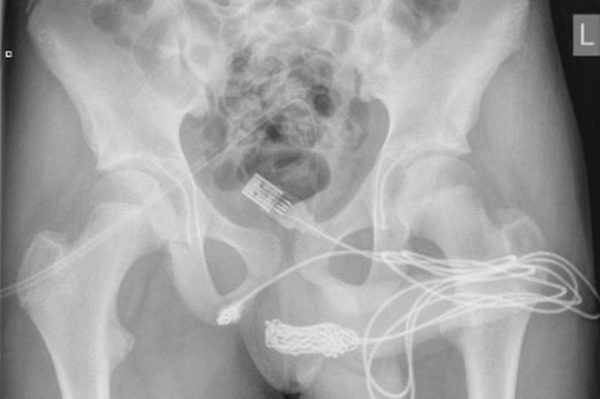

疼痛难耐的少年立即附近医院求医,医生检查发现数据线已在其体内打结。

“数据线的两端在尿道口外,但中间打结的部分仍留在其尿道里。”

据报道,医生起初将金属制的空心管塞入少年的尿道口,企图制造空隙取出数据线,却因数据线在阴茎内打结而失败。

医生不得不切开生殖器与肛门之间的部分,从下方接触到数据线,才成功完成手术。